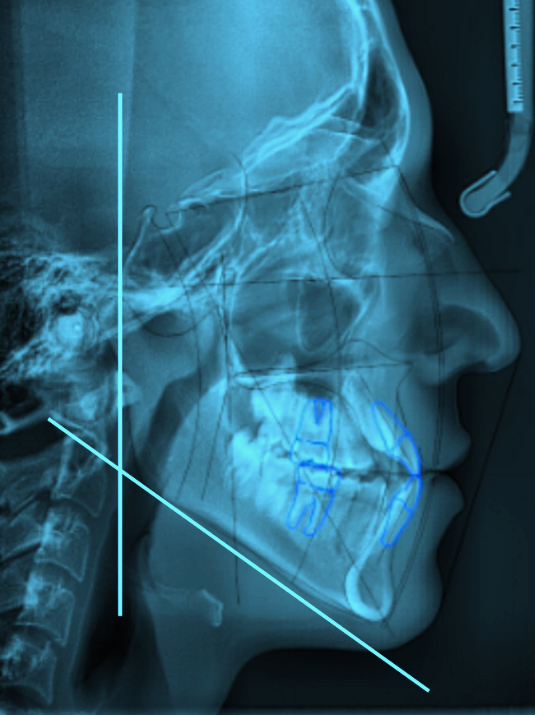

Здравствуйте всем. У меня остеотомия нижней челюсти, на приеме челюстно-лицевой хирург сказал что нужно делать операцию по исправлению прикуса и лицевого отдела черепа как можно быстрее. Оказалось что это "удовольствие" не дешевое и требуется порядка 250 тысяч рублей. Я со своей зарплатой гардеробщицы которой едва хватает на существование, денег таких не соберу никогда. Поэтому выход у меня один, просить добрых людей о помощи. Прошу вас пожалуйста помогите мне сделать эту операцию, прошу вас. Вот карта для помощи - 2204 1201 1992 5101